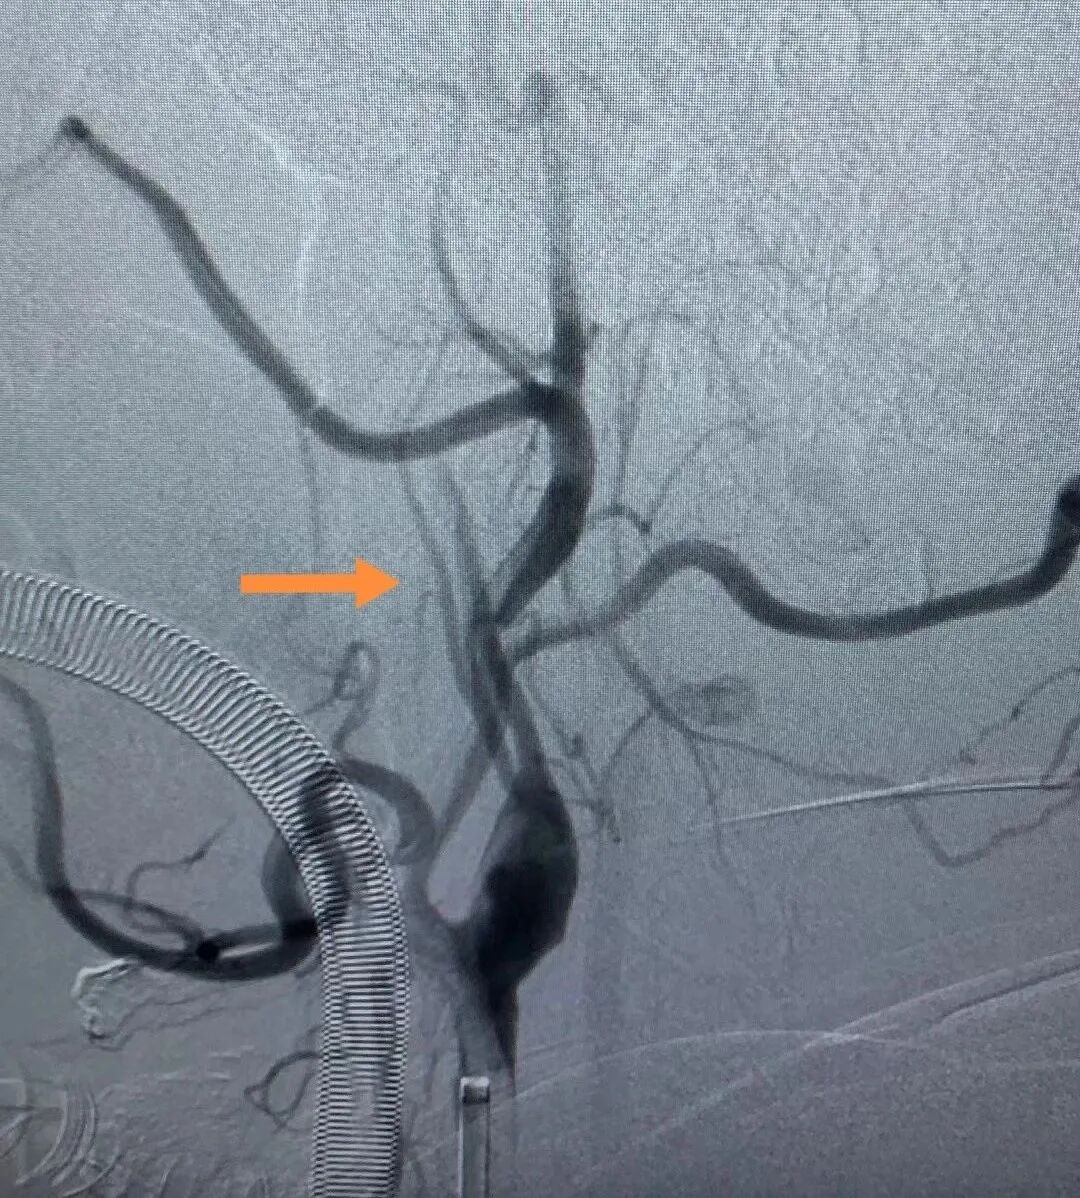

術(shù)前DSA影像

經(jīng)檢查,患者頸內(nèi)動(dòng)脈急性閉塞,斑塊脫落至眼動(dòng)脈遠(yuǎn)端,栓塞眼動(dòng)脈,情況十分危險(xiǎn)!經(jīng)過(guò)黃志勇主任醫(yī)師、景英朝主任醫(yī)師、李江副主任醫(yī)師等卒中專(zhuān)家的迅速評(píng)估后,果斷為患者進(jìn)行了介入手術(shù)治療,先開(kāi)通頸內(nèi)動(dòng)脈急性閉塞的血管,保證顱內(nèi)供血,然后通過(guò)溶栓治療,讓眼動(dòng)脈恢復(fù)供血,保證視力。目前,患者已病情穩(wěn)定。